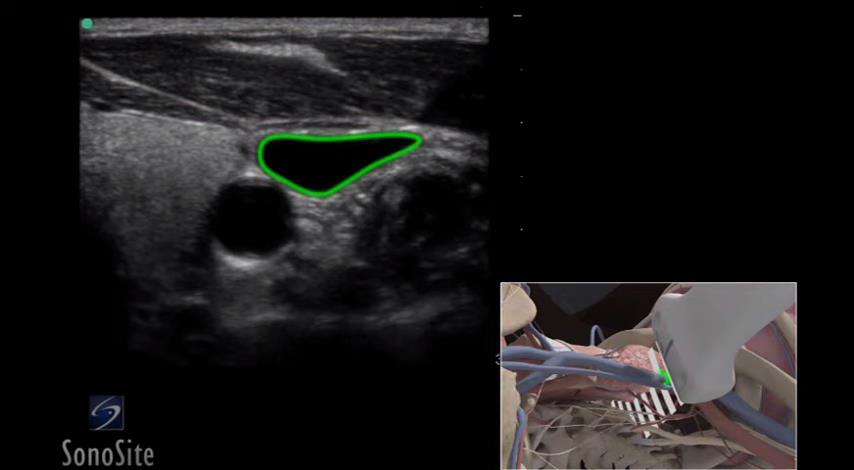

超声引导下静脉通路建立

98 #B超定位穿刺